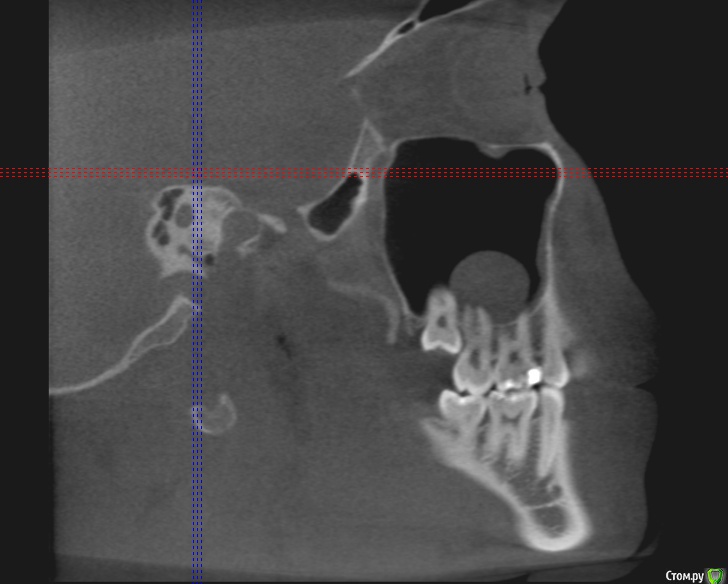

Добрый день коллеги,плановое удаление 8 зубов ,верхние в гайморовой ,что за образование в левой жалоб нет никаких.Что вы делаете при вскрытии пазухи?